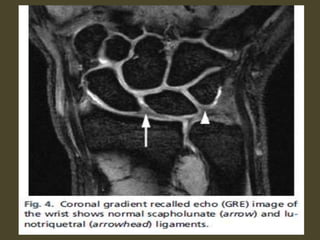

Scapholunate and lunotriquetral ligament tear.